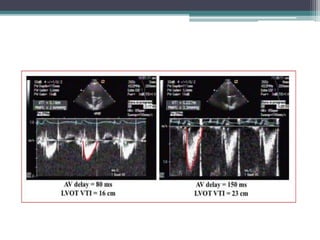

Atrioventricular delay

• Atrial contraction contributes 20 –30% to stroke

Iterative Method

• Objective:

▫ Identify the AV Delay that maximizes LV filling using mitral

velocity echocardiographic measurements1

• Procedure

▫ Obtain transmitral Doppler echo at a “long” programmed AV Delay

during ventricular pacing

▫ Shorten the programmed AV Delay by 10-20 ms until the echo

Doppler A-wave becomes truncated (A wave is atrial contraction)

▫ Lengthen the programmed AV Delay back to the value where there

is no A-wave cutoff. This timing should enable ventricular

contraction to occur just at the end of atrial systole

• to maximize DFT

(i.e. separation of

the E- and A-

waves).

• to allow complete

end-diastolic

filling(marked by

the end of the A-

wave)before the

onset of LV

contraction.

Optimal AV delay is

1. E and A wave separated.

2. Termination of the A wave at

approximately 40 to 60 milliseconds before

the onset of the QRS.

3. Stage I diastolic filling pattern i.e A > E